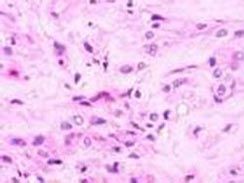

組織病理檢查可見擴張的血管和梭形細胞兩種組織結構,可見細胞多形性和核分裂象。網硬蛋白染色見個別細胞和成群細胞外方繞有網狀纖維。免疫組化檢查,第8因子相關抗原和荊豆植物血凝素陽性。上皮膜抗原和細胞角蛋白染色通常為陰性。